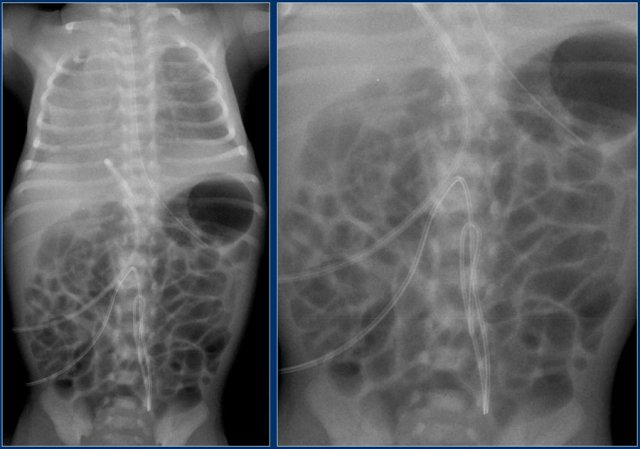

Umbilical artery line (4)

First study the images.

Then continue reading.

The findings are:

1. Deep position of umbilical artery line, in aortic arch.

2. Umbilical vein line with tip in right portal vein.